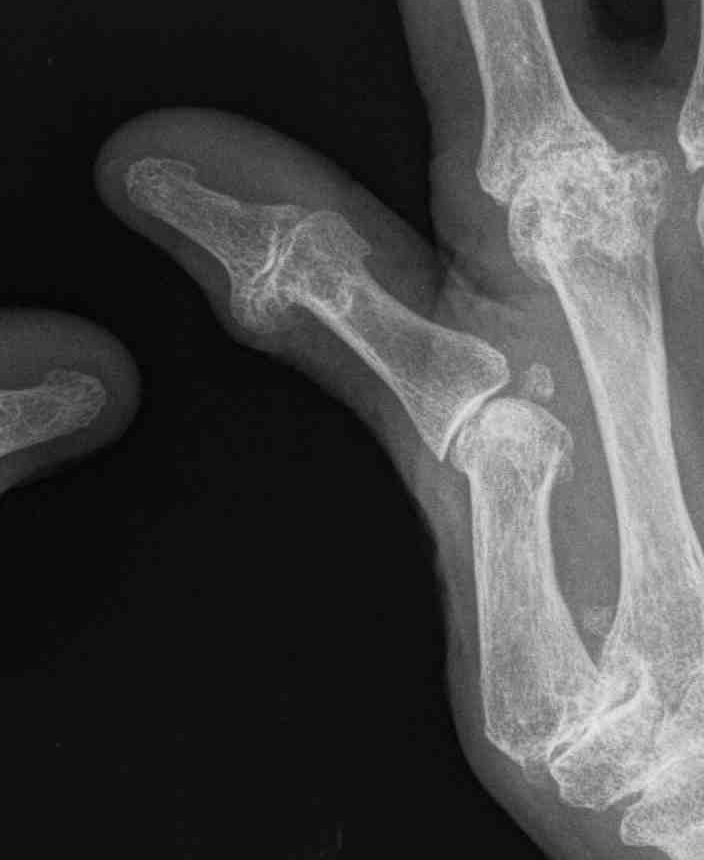

Type I - Boutonniere

- commonest

- MP flexion / IP hyperextension

- usually EPB rupture with EPL subluxation